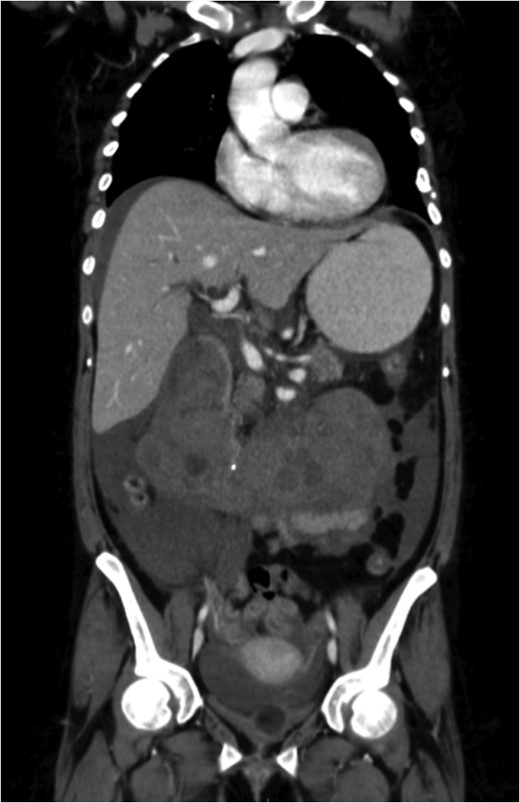

A venous phase abdominal CT demonstrating the end of the IVC filter strut penetrating the wall of the third part of the duodenum.

A coronal section of a venous phase abdominal CT demonstrating the end of the IVC filter strut penetrating the wall of the third part of the duodenum.